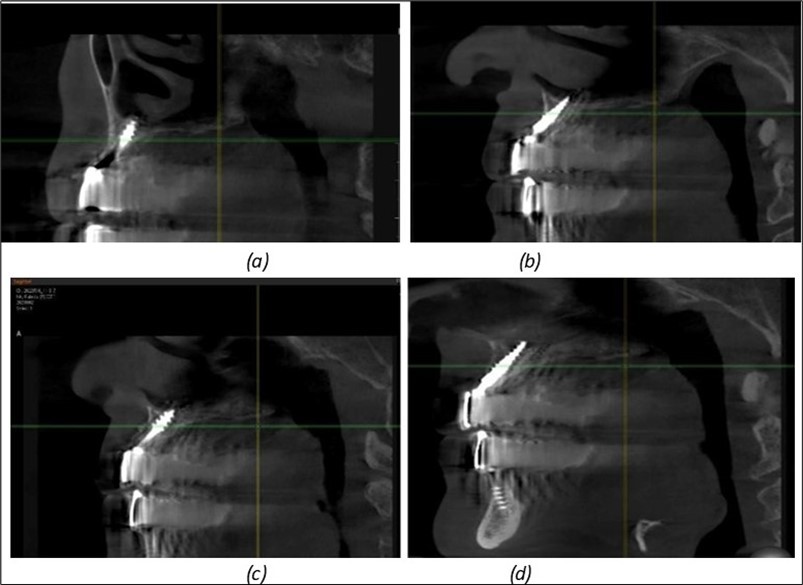

A total of 11 implants is placed in the maxilla, including compressive TPG implants with a polished surface in the maxillary-sphenoid fusion area (Figure 3, Figure 9). Similarly, in the anterior region, final fixation is achieved in the nasal cortex, and BCS corticobasal implants are added in areas with massive bone loss in the frontal region (Figure 3, Figure 8, Figure 11). Additionally, in the palatal sinus cortical area, with the aim of avoiding the addition and sinus lift zone where the second cortical bone no longer exists, 3 implants are placed, 2 in quadrant 1 and 1 in quadrant 2 (Figure 3, Figure 8). Through the Caldwell-Luc sinus lift procedure, the sinus cortical bone is displaced to allow the placement of the graft material and elevation of the sinus membrane. This sinus cortical is no longer recreated at the junction of the graft material and mucosa-sinus membrane, making it impossible to place a corticobasal implant, which relies on the second cortical bone. In the distal mandibular area, after the removal of two stage implants due to massive destruction in quadrant 3, implant placement distal to the mylohyoid line is not possible, as in quadrant 4 (Figure 10). A re-intervention occurs after 5 months to stabilize the area (Figure 12, Figure 14). Also, at the moment of fixation, the tip of one implant fractures, and the decision is made to leave it in place due to regional bone destruction, in order to avoid enlarging the bone defect.

Figure 9.Implants in the pterygoid plateau area: (a) TPG implant fixed in the maxillary-sphenoid junction area, quadrant 1; (b) TPG implant fixed in the maxillary-sphenoid junction area, quadrant 2.

Journal of Dentistry and Oral Implants - Periimplantitis

Figure 13.Corticobasal BCS implants fixed between the vestibular and lingual cortices with support on the basal bone: (a) BCS fixed between the lateral cortices; (b) BCS implant with support on the basal cortex.

Figure 14.Rx panoramic final situation control: (a) Panoramic X-ray with the addition of a distal BCS implant in quadrant 3 at 11.2022; (b) Control X-ray, 10.2023.